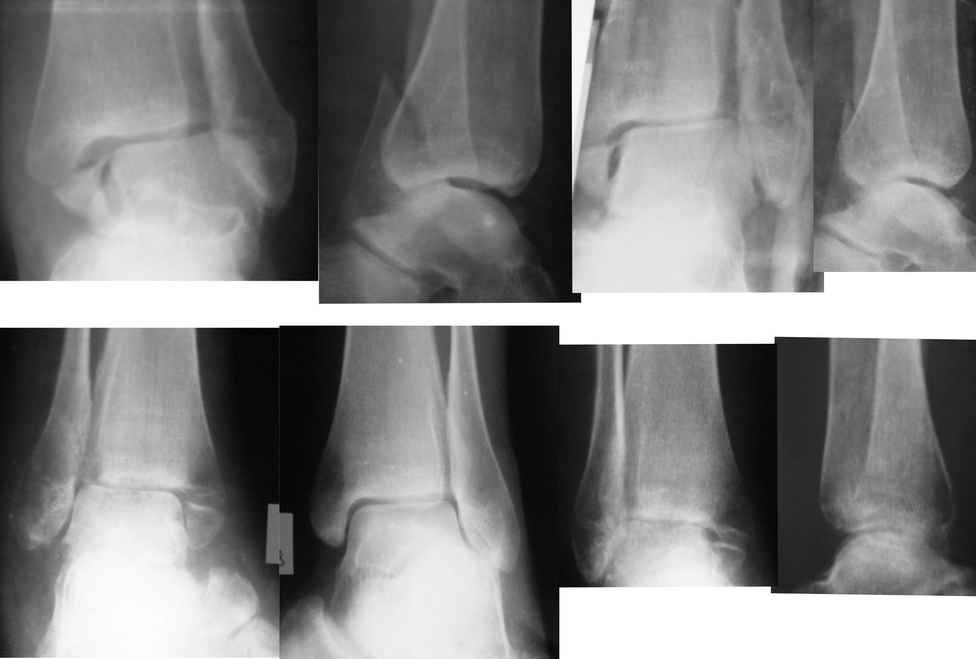

Евгений!. Вы сами ответили на вопрос. Оперировать безусловно, восстановить длину малоберцовой кости, позиционный винт и винты на внутреннюю лодыжку. Послеоперационное ведение как при свежем переломе, отсчет от дня операции, о потерянных двух месяцах придется больной забыть.

Единственное, в таких случаях более мощную пластину взамен классической 1/3 трубки предпочитаю выбирать. Или переходную метафизарную, что дороже. Или реконструктивную. Что бюджетнее.

Проволочный серкляж для внутреней лодыжки приведет к значительно большей травматичности вмешательства. Вполне можно обойтись 2 спицами или спицей и винтом. Все-таки основное внимание должно быть уделено наружной лодыжке. И, учитывая имеющийся регионарный остеопороз, лучше пусть будет более тонкая блокируемая пластина, чем мощная без возможности блокирования.

Вот только исходя из личного опыта считаю, что через два месяца после травмы позиционного винта на синдесмоз будет мало, не обойтись без старого доброго болта-стяжки, (по крайней мере у меня не получалось, это не свежая травма). Тем более послеоперационный период предполагается без внешней иммобилизации с ранним включением функции.